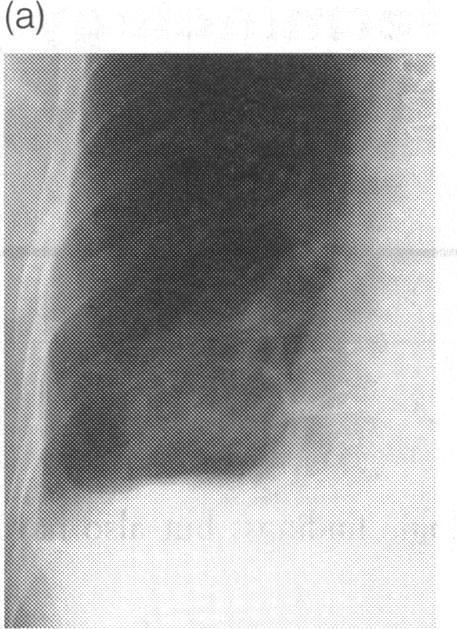

Woodard P K, McAdams H P, Putman C E

Department of Radiology, Duke University Medical Center, Durham, North Carolina 27710, USA.

J R Soc Med. 1995 Dec;88(12):669-71. doi: 10.1177/014107689508801204.